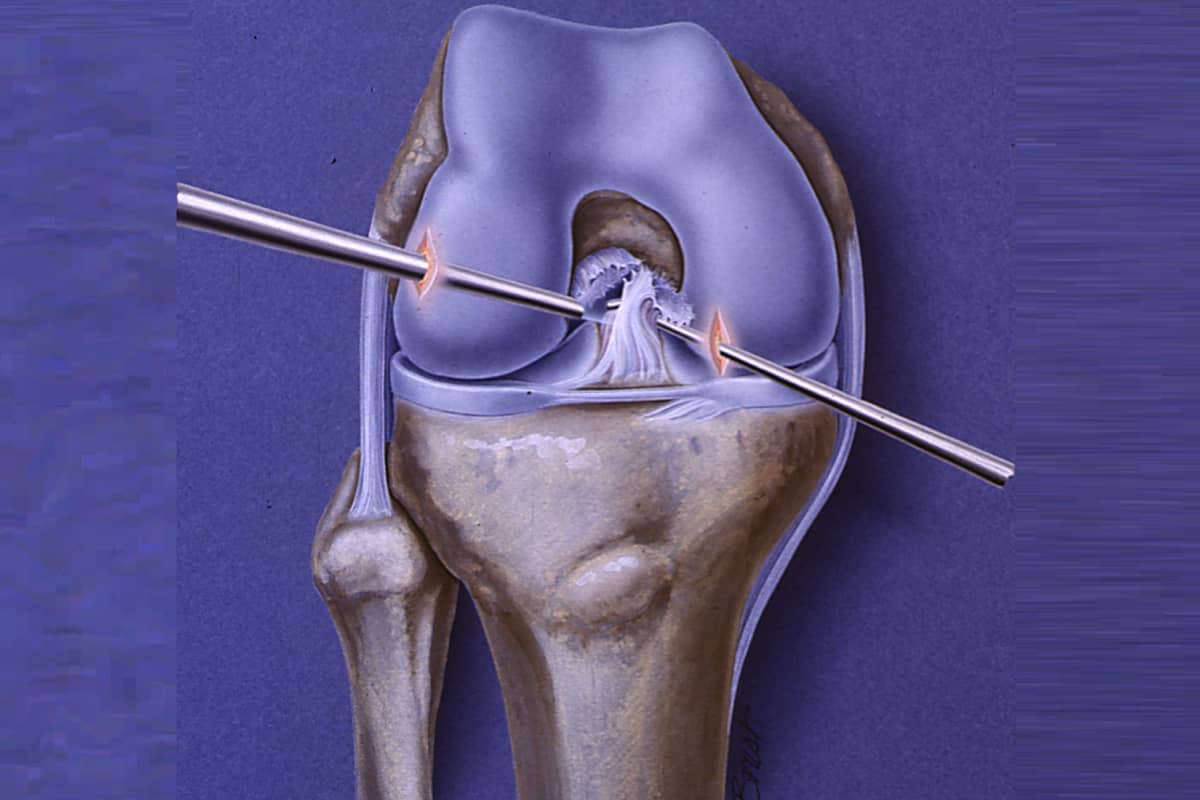

Meniscus surgery, performed arthroscopically, is a minimally invasive procedure used to either repair or remove a torn meniscus.

Anterior Cruciate Ligament (ACL) is an key ligament found inside the knee joint. It sits diagonally in the

Both the ACL (Anterior Cruciate Ligament) and PCL (Posterior Cruciate Ligament) are crucial ligaments within the knee joint.